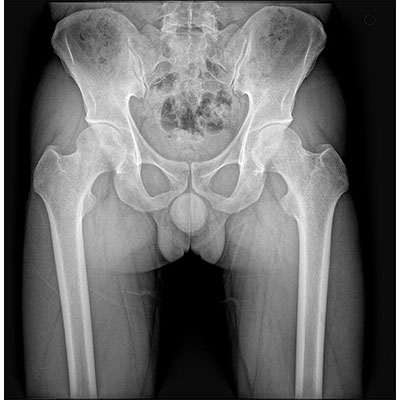

● 采用自主研發(fā)的技術(shù),在保證優(yōu)質(zhì)圖像的前提下,大大降低X射線劑量,用心呵護(hù)醫(yī)護(hù)工作者及患者的健康。

● 短曝光時間,便于老年人、兒童、殘疾人進(jìn)行臨床拍攝。避免這類群體因不能有效控制身體運(yùn)動等因素造成的運(yùn)動偽影,提高攝片質(zhì)量及效率。